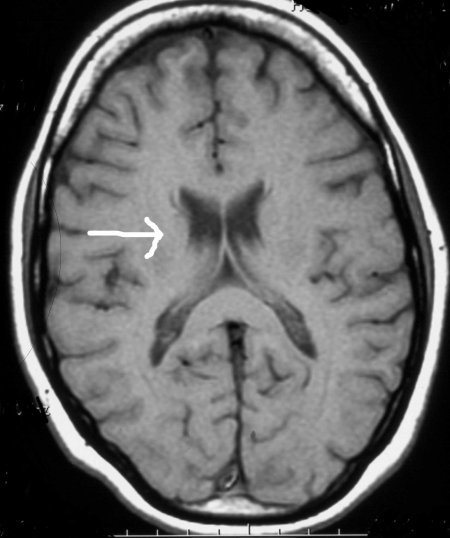

Ci-dessous, nous pouvons observer une IRM (Imagerie par Résonance Magnétique) d'un cerveau normal, vous remarquerez une petite flèche qui vous montre les ventricules latéraux, ce sont des poches habituellement petites contenant le liquide cérébro-spinal. Elles sont sombres. Je ne vais pas rentrer dans les détails, restons simples.